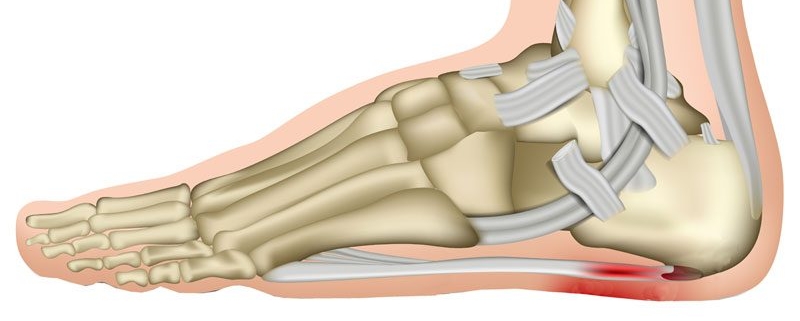

خدمات این کلینیک شامل تشخیص و درمان مشکلات مرتبط پا، مشکلات استخوانی و مفصلی پا، مراقبت و درمان زخمهای پا، کشیدگی عضلات، میباشد. همچنین، این کلینیک به ارائه خدمات مراقبتی پا برای بیماران مبتلا به دیابت نیز میپردازد.

کلینیک سلامت پا پردیس با سابقه چندین ساله، به عنوان اولین مرکز تخصصی اسکن پا در این منطقه، به ارائه خدمات اسکن کامپیوتری پا و درمان غیرجراحی مشکلات مربوط به صافی کف پا، آرتروز زانو، انحراف زانوی ضربدری و پرانتزی، درمان خار پاشنه و میخچه، درمان درد ساق پا و کف پا، و درمان انحراف مفصل مچ پا مفتخر است.

کلینیک سلامت پا در تهران و کرج، با سابقه چندین ساله و به عنوان اولین مرکز تخصصی اسکن پا مفتخر به ارائه خدمات اسکن کامپیوتری پا و درمان غیرجراحی در صافی کف پا، آرتروز زانو، انحراف زانوی ضربدری و پرانتزی، درمان خار پاشنه و میخچه، درمان درد ساق پا و کف پا، درمان انحراف مفصل مچ پا می باشد. این کلینیک مجهز به جدیدترین و مدرن ترین دستگاه های اسکنر پا با تکنولوژی کشور آلمان می باشد و آماده خدمت گزاری با استفاده از جدیدترین روش های تشخیصی و درمانی است.